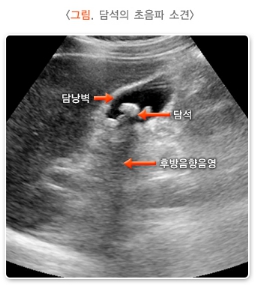

- 초음파 검사: 담석 유무, 담낭의 크기와 모양 등을 확인합니다.

- 검사 종류: 초음파 검사는 담석 유무를 확인하는 가장 간단하고 정확한 방법입니다.